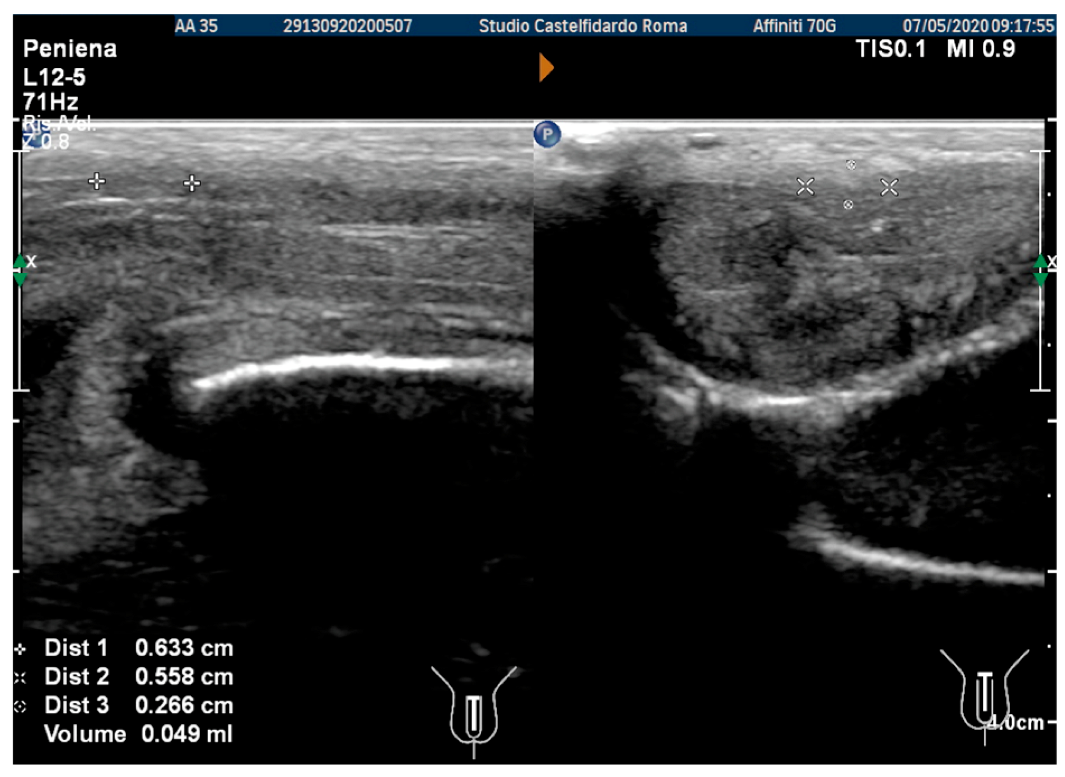

| 2 | 32 years | lichen sclerosus, chronic prostatitis | Proximal third | (A) 16.4 × 8.27 × 3.09 mm volume = 219 mm3 | (A) 10-degree left curvature | (A) score 3 | (A) score 26 | 2 years and 9 months | orally: Silymarin 400 mg + Ginkgo biloba 250 mg + Propolis 600 mg + Bilberry 160 mg + Vitamin E 800 IU/once a day, for 33 months. + topically: Propolis creme/twice a day/for 33 months. + peri-plaque penile injections: Pentoxifylline 100 mg (30 G needle) every 15 days for 6 months, and then monthly for 12 months, and then 1 injection every other month. for 12 months (total = 30 injections) |

| (B) No plaque detected | (B) None | (B) score 0 (after six months) | (B) score 28 | ||||||